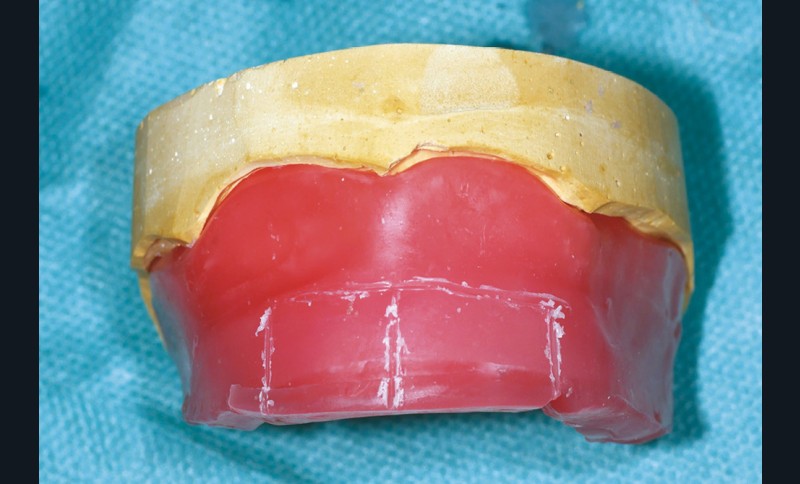

Au maxillaire, la largeur du bourrelet est d’environ 6 à 8 mm en postérieur et doit suivre les aires de tolérance. En antérieur, sa largeur est de 4 mm et doit être monté en avant de la papille rétro-incisive de 6 mm environ afin de compenser la résorption osseuse. Il est incliné d’environ 10 à 15° vers l’avant. La hauteur mesurée du bord incisif au fond de sillon est d’environ 21 mm (fig. 5).

La maquette maxillaire est désormais réglée et ne doit plus être modifiée (fig. 16). Elle peut être conservée dans un bol d’eau froide pour éviter les distorsions.